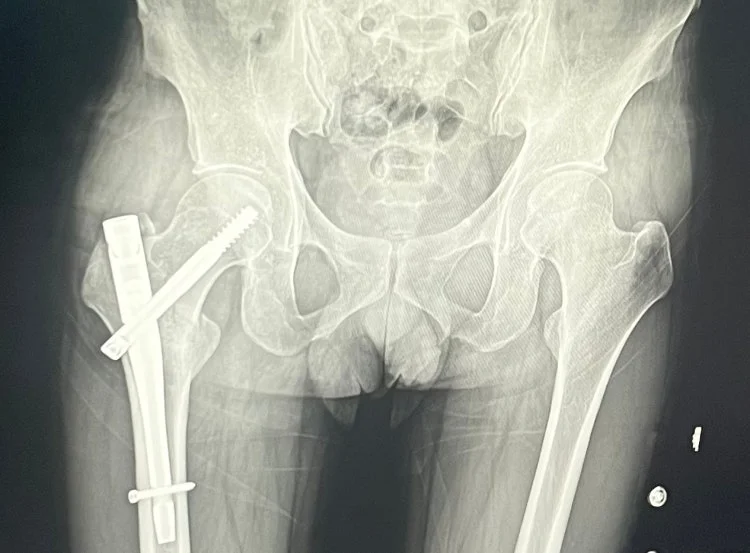

엑스레이상 수술은 잘된건지,

Dr.s Diagnosis안녕하세요. 대퇴부 전자간 골절 수술 후 회복 중이신 환자분의 질문에 답변드리겠습니다. 사진과 함께 자세한 내용을 보내주셔서 감사합니다.

1. 엑스레이상 수술은 잘 된 건지:

환자분께서 첨부해주신 엑스레이 사진은 제가 직접 판단할 수 없지만, 일반적으로 엑스레이 검사 후 의사 선생님께서 "수술이 잘 되었다"라고 말씀하셨다면 뼈의 정렬이나 고정 상태가 양호하다는 의미입니다. 하지만 엑스레이 사진만으로는 모든 것을 판단할 수 없으며, 임상적인 증상과 경과를 함께 고려해야 합니다.